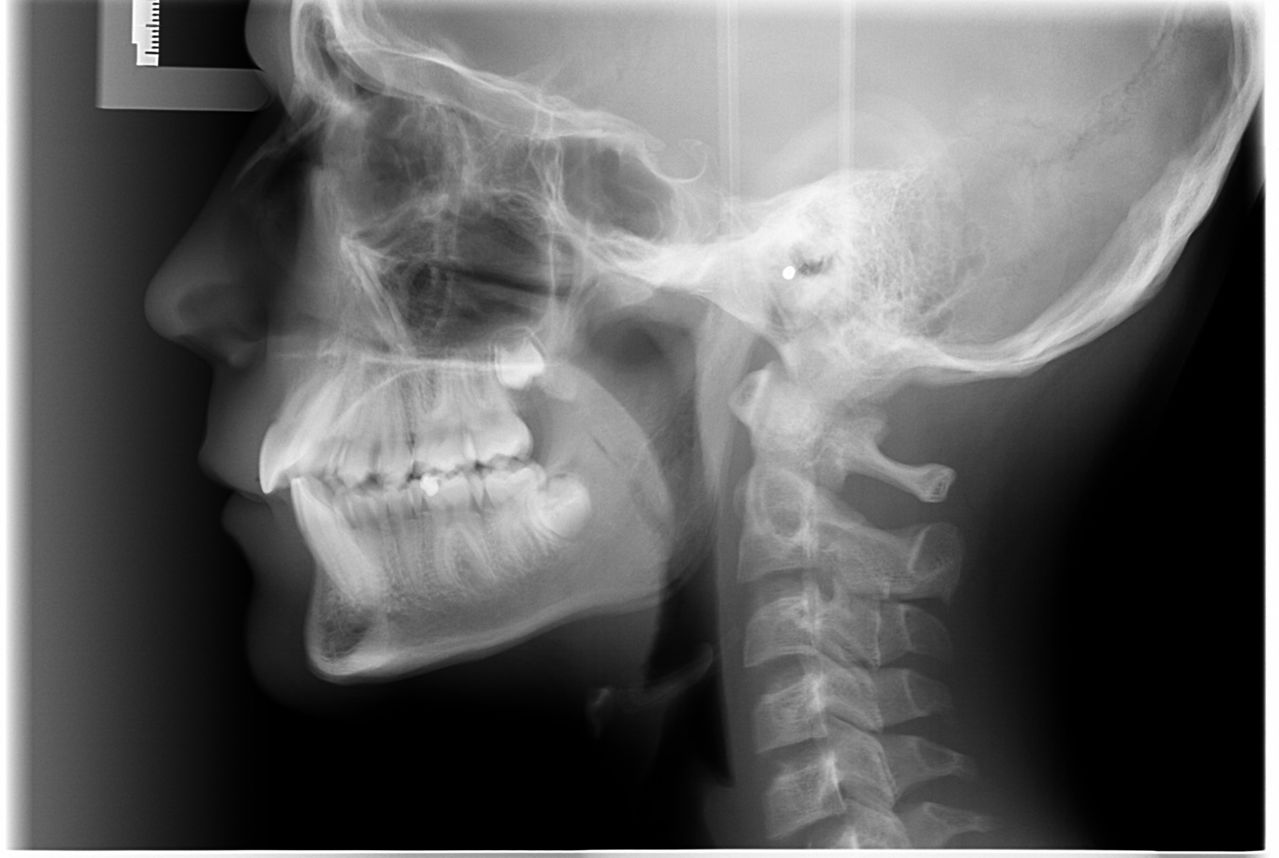

- Vi tager røntgenbilleder af tænder, kæber og hoved.

Der tages desuden fotos af tænderne og ansigtet samt røntgenbilleder.